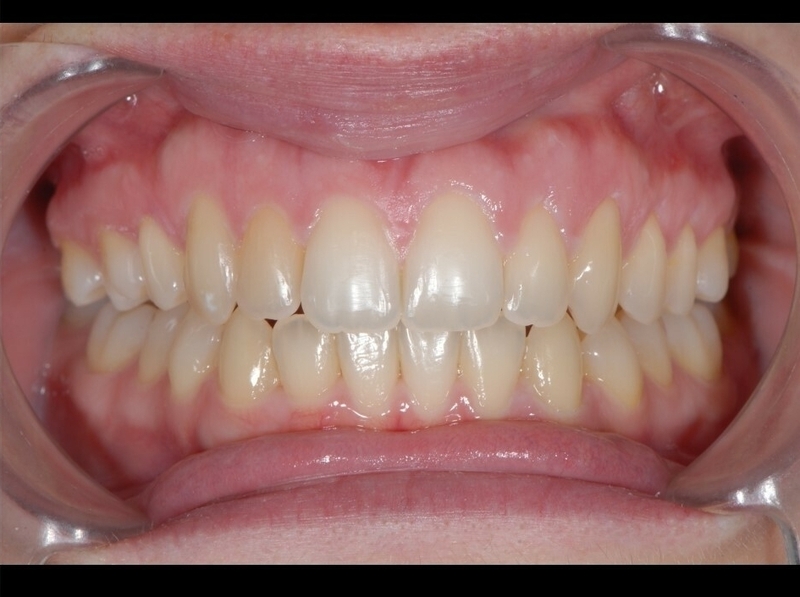

Avant

Après